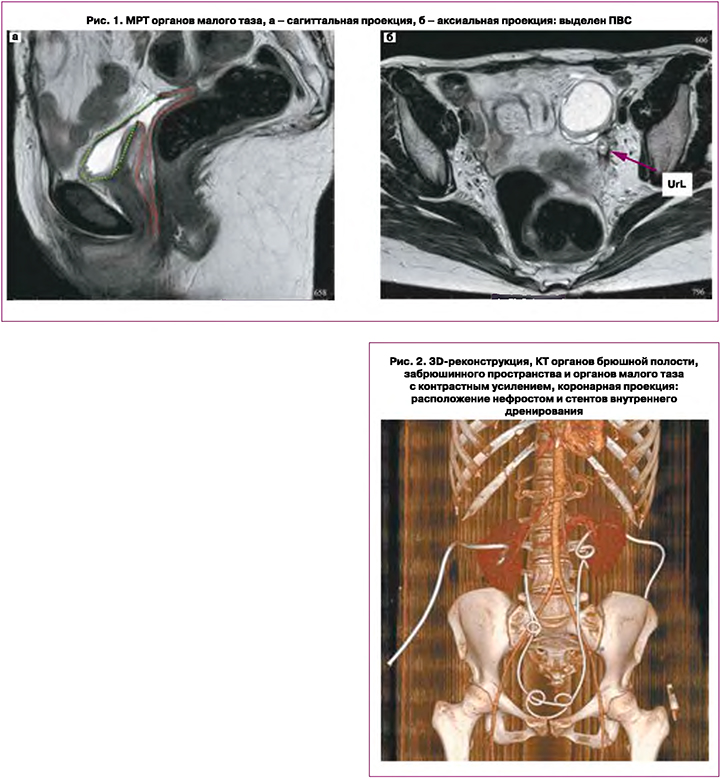

С октября 2021 г. вновь отмечено выделение мочи из влагалища, верифицирована дислокация нефростомы из расширенной лоханки правой почки. 15.11.2021 г. пациентка госпитализирована в ФГБУ «Национальный медицинский исследовательский центр хирургии им. А.В. Вишневского» Минздрава России (далее – НМИЦ хирургии им. А.В. Вишневского) с целью хирургического лечения. При дообследовании выполнена магнитно-резонансная томография (МРТ) органов малого таза, подтвердившая наличие ПВС (рис. 1). Протяженность дефекта стенки мочевого пузыря составляла 0,7 см, дистальный край свища располагался на расстоянии менее 1,5 см от меатуса, вокруг свища имел место умеренный фиброз. Объем мочевого пузыря не превышал 30 мл.

По данным КТ органов брюшной полости, забрюшинного пространства и органов малого таза с контрастным усилением, состояние после нефростомии с двух сторон, установки интегральных стентов мочеточников, миграция стента правого мочеточника. Признаки перенесенного двустороннего пиелонефрита (рис. 2).